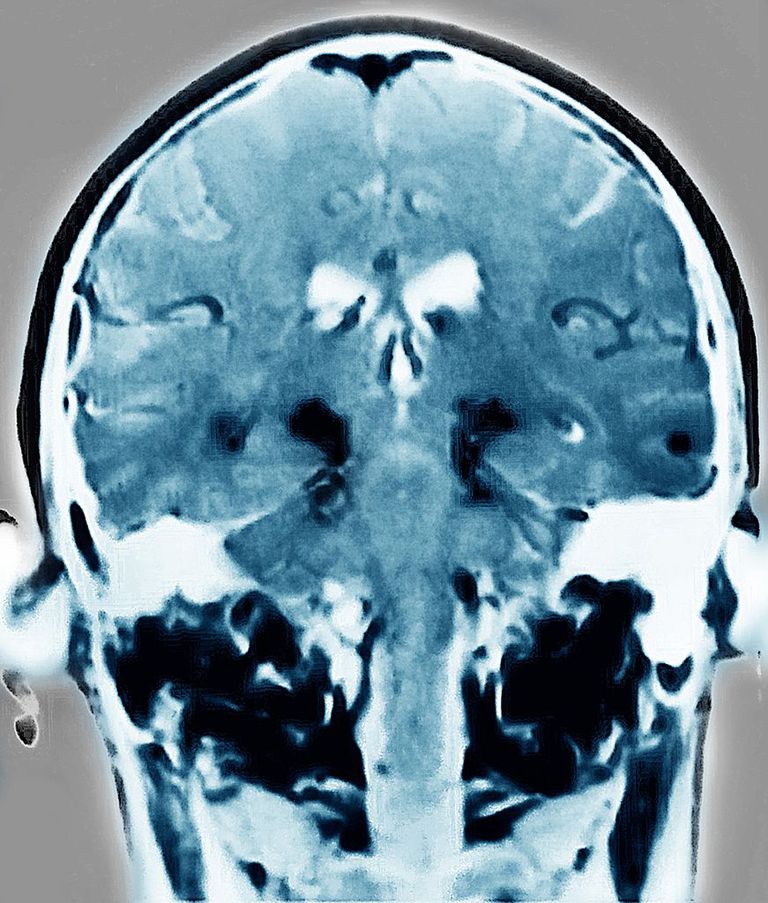

Un mes después de la inyección, los investigadores observaron que la α-sinucleína se había diseminado al núcleo motor dorsal del vago, ubicado en la parte más baja del tronco cerebral; en tres meses, se había extendido por el tronco cerebral al locus cerúleo, a la amígdala, el hipotálamo y a la corteza prefrontal. A los siete meses, la α-sinucleína patológica se había extendido a regiones adicionales del cerebro, como el hipocampo, el cuerpo estriado y el bulbo olfatorio.

En este momento, también hubo una pérdida significativa de neuronas productoras de dopamina en el sistema nervioso central. Además de las deficiencias motoras, los ratones que recibieron las inyecciones desarrollaron signos de depresión y ansiedad, disfunción olfatoria y deficiencias cognitivas que afectan el aprendizaje espacial y la memoria, el reconocimiento de nuevos objetos, la memoria del miedo y la memoria funcional. La transmisión de la proteína y los efectos resultantes, no se produjeron en ratones cuyo nervio vago había sido seccionado.